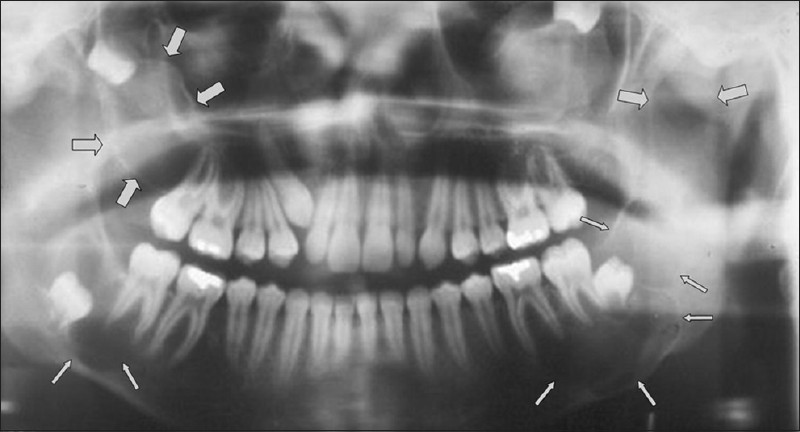

Dentigerous Cyst

Cyst tht originates by separation of the follicle from the crown of unerrupted tooth.

Accumulation of fluid between the REE and tooth crown

Follicular space is larger than 3mm

Encloses the crown of the unerrupted tooth and is attached at the CEJ

Completely asymptomatic – discoveredon routine xray

XRAY: UNILOCULAR radiolucency, well defined (sclerotic border)

Most commonly associated with 3rd molars